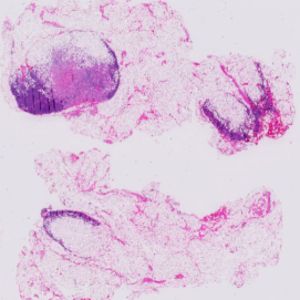

NCRF 是一种神经条件随机场结构,能够将检测到的癌症转移到WSI 中。这种框架通过完全连接的条件随机场(CRF),将相邻补丁之间的空间相关性直接并入CNN 结构的顶层特征提取器,并采用标准的端到端训练方式,以反向传播法进行优化。实验结果表明这种框架能够获得更佳质量的预测概率图,并取得不错的平均FROC 分数。